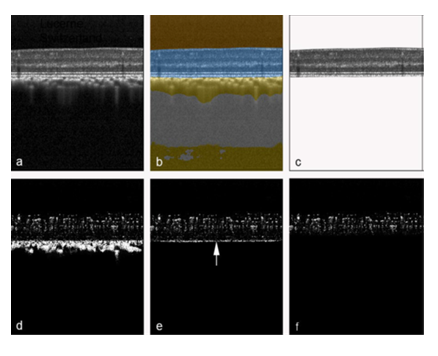

The focus of this study was to infer OCTA data from raw OCT data. In the first step (Fig. 1) a previously developed and validated deep learning network [29] was used to extract retina (Figure 1b) from the original OCT structural B-scan. In the second step, from the original OCTA B-scan, masks were created to extract only the OCTA signal from the retina (Fig. 1d). The extracted OCT and its corresponding original OCTA image were then used as the expected image pair for the training of the deep learning algorithm.

Figure 1: Automatic retina OCT and OCTA segmentation. An original OCT B-scan (a) was processed using a validated deep learning algorithm to compartmentalize the retina (b, highlighted in blue), which was then extracted from the remaining tissue (c). The corresponding original OCTA scan from the same position, generated by the manufacturer's OCTA software (d), was accordingly delineated at the border between retinal pigment epithelium and choriocapillaris (e). Then, all pixels below a virtual line located 20 pixels above the inner edge of the choriocapillaris-retinal pigment epithelium complex (e, arrow) were masked to remove hyperreflective regions not belonging to the retinal OCTA signal. This procedure resulted in a structural retinal B-scan (c) and its corresponding OCTA B-scan (f), which were subsequently utilized for training and testing of the deep learning algorithm.